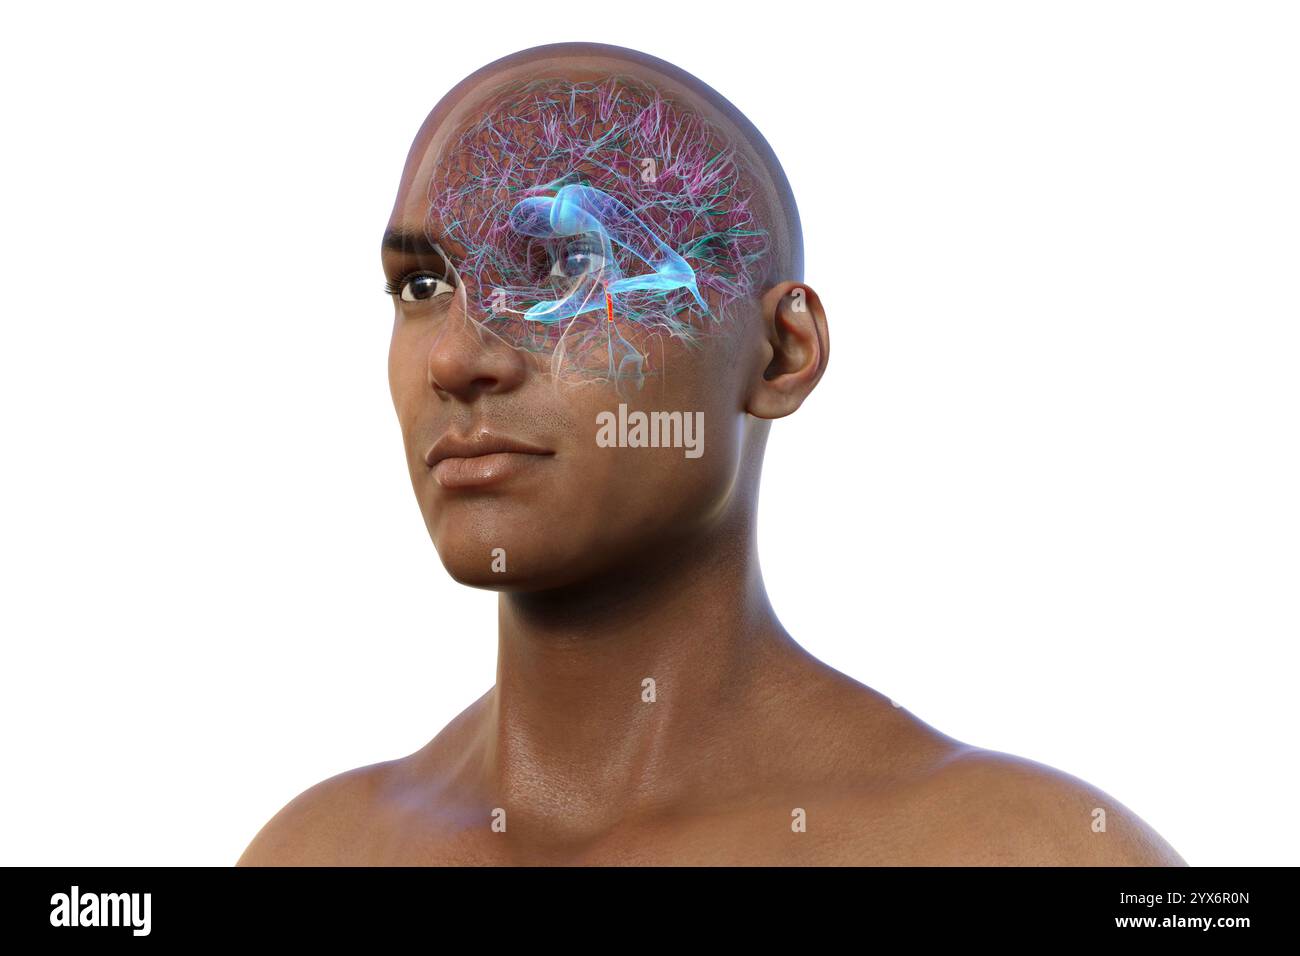

RF2YX6R0N–Computerdarstellung des menschlichen Gehirns mit orangefarbenem Aquädukt und grünem Ventrikelsystem, die den Liquorfluss (CSF) zeigen.

RF2YX6R0K–Computerdarstellung des menschlichen Gehirns mit orangefarbenem Aquädukt und grünem Ventrikelsystem, die den Liquorfluss (CSF) zeigen.

RF2YX6R02–Computerdarstellung des menschlichen Gehirns mit orangefarbenem Aquädukt und grünem Ventrikelsystem, die den Liquorfluss (CSF) zeigen.

RF2YX6R05–Computerdarstellung des menschlichen Gehirns mit orangefarbenem Aquädukt und grünem Ventrikelsystem, die den Liquorfluss (CSF) zeigen.

RF2YX6R0G–Computerdarstellung des menschlichen Gehirns mit orangefarbenem Aquädukt und grünem Ventrikelsystem, die den Liquorfluss (CSF) zeigen.